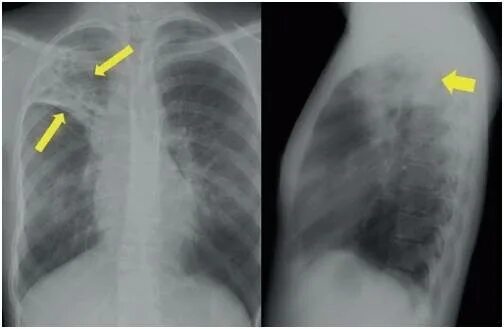

Фиброзное изменение левого легкого